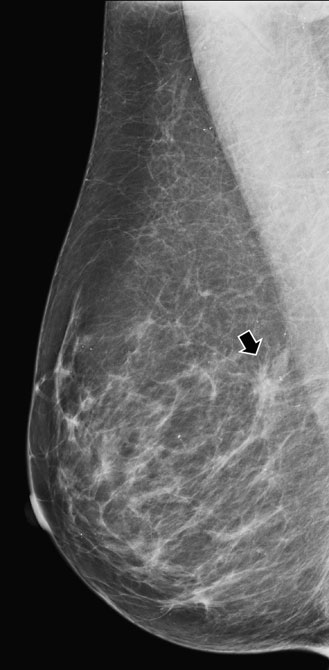

Palpable mass in the upper breast

Palpable mass in the upper breast shown on mammography to be irregular.

MR MIP image

MR MIP image again shows the irregular mass in the upper outer breast. Histology revealed a T2, N0, M0 invasive ductal carcinoma (ER/PR +, Her-2 neu -) and high-grade ductal carcinoma in situ.